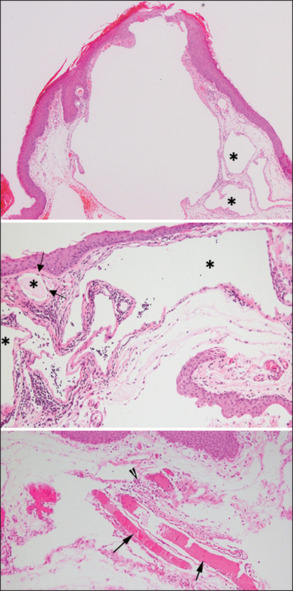

Results: All patients had unilateral conjunctival involvement. The mean age was 48.9 ± 18.9 years, with more women affected (67%). No patient had impaired visual acuity secondary to the lesion. The location of the lesion was temporal in 67% of patients. The presenting symptoms included conjunctival swelling, discomfort and/or foreign-body sensation, and tearing. All lesions were excised, and none recurred. All excised lesions showed dilated channels that were lined by a flattened endothelium staining positive with CD34, surrounded by edematous lamina propria. Larger ectatic lymphatic channels demonstrated scattered D2-40 staining in the endothelial cell lining and patchy CD34 staining within the endothelial cell cytoplasm. D2-40 and CD-34 immunoreactivity did not overlap in the same cells.

Conclusion: The clinical features and outcomes of the lesions in this large cohort were similar to those reported in the literature. However, the mixed immunoreactivity of the endothelial cells lining these ectatic lymphatic channels in the conjunctiva suggests that these channels are lymphatic-venous lesions. We suggest that these channels be termed conjunctival lymphaticovenous malformation rather than lymphangiectasia, which suggests ectasia of existing lymphatics. Future studies are needed to understand these lesions and their histopathologic origins.